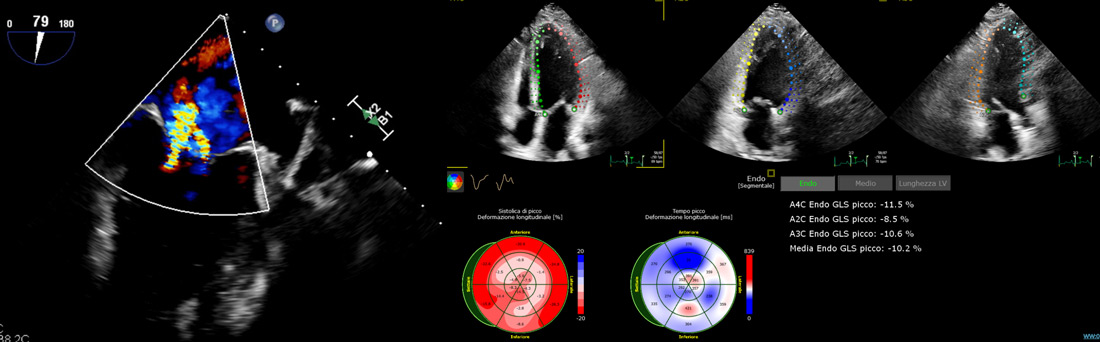

TOE showed post-infarction cardiomyopathy with mildly reduced left ventricular ejection fraction (LVEF 40-43%).

Persistent moderate-to-severe functional mitral regurgitation due to posterior leaflet tethering and anterior leaflet sliding.

Left ventricle of normal dimensions and wall thickness (LVEDD 53 mm, IVSd 10 mm, PWd 10 mm). Moderately reduced systolic function (LVEF 45%) with inferoposterior akinesia and hypokinesia of the mid-distal interventricular septum. Grade II diastolic dysfunction (E/e′ 9). Mild-to-moderate mitral regurgitation. Right heart chambers within normal limits (TAPSE 20 mm). Mild tricuspid regurgitation; estimated PAPs 25 mmHg.